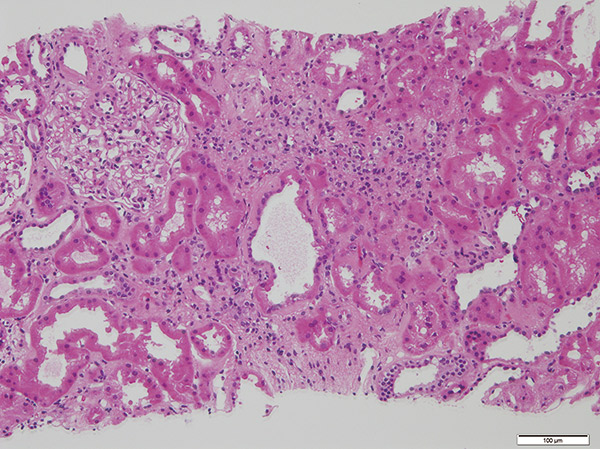

症例は50歳代男性。2016年6月、脳死ドナーからの血液型適合献腎移植を受けた。移植後に拒絶反応があったが、 治療後は良好に経過していた。2023年4月の外来定期検査で血清クレアチニンが上昇し、急性拒絶を疑い移植腎生検を実施した。病理所見では、尿細管上皮はよく保たれており一部に萎縮とリンパ球浸潤(t1)、間質の線維化は軽度(i1)、糸球体血管腔は拡張してリンパ球、好中球浸潤なし(g0)、小・細動脈壁に硝子変性、細胞浸潤なし(v0)、ptc0、C4d on PTCは陽性であった。また、抗HLA抗体スクリーニング検査でClassII抗体陽性のため急性抗体性拒絶と診断した。